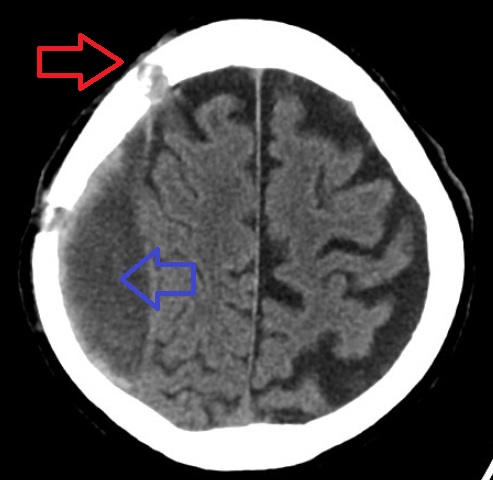

Ct-scan of the brain with an subdural hematoma.

Chronic subdural bleed with old burr holes.